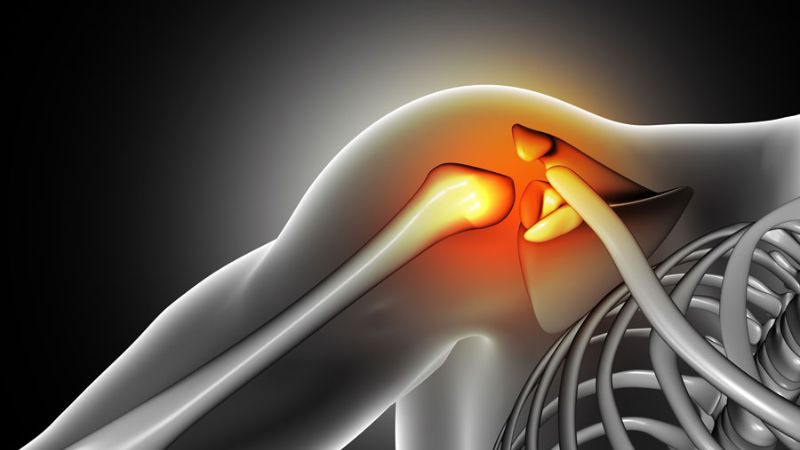

Viêm khớp

Khớp vai xuất hiện tình trạng viêm có thể khiến cho các tế bào hệ miễn dịch hoạt động gây nên triệu chứng sưng, nóng, đỏ và đau của khớp vai. Ngoài ra, tình trạng viêm khớp mạn tính như viêm khớp dạng thấp hay viêm xương khớp cũng khiến cho cấu trúc vùng vai bị phá vỡ và gây đau.

Viêm khớp có thể khiến cho vai bị sưng đau